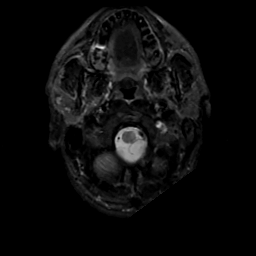

MR Study #10, April 28, 1991 -- Slice #2